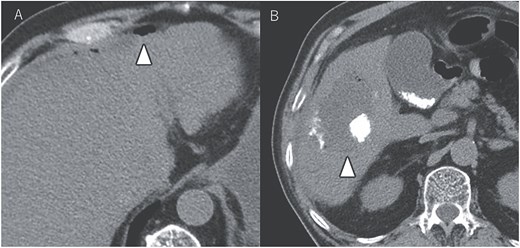

After seven courses of treatment, he was transported to our emergency department because of abdominal pain. CT revealed ascites and free air on the liver surface as well as air within the liver tumor (Fig. 3). Peritonitis was diagnosed, and emergency laparotomy was performed. Strong adhesions were observed between the liver tumor, greater omentum, and the colon. Although small amounts of turbid ascites were found, no obvious perforations were observed in the stomach, duodenum, or small intestine. Abdominal lavage and drainage were performed. Postoperatively, persistent fever and elevated levels of inflammatory markers were noted. Subsequent CT revealed a fluid collection with air within the liver tumor and thickening of the gallbladder wall (Fig. 4A). The patient was diagnosed with a liver abscess secondary to HCC necrosis and cholecystitis, and percutaneous transhepatic drainage of the liver abscess and gallbladder was performed. Seven days after the drainage, fistulography through the liver abscess drainage catheter revealed colonic opacification (Fig. 4B). CT revealed the liver tumor adjacent to the catheter with opacification of the colonic lumen (Fig. 4C). Based on these findings, a diagnosis of hepatocolic fistula secondary to HCC was made. Considering the low likelihood of natural closure, loop ileostomy was performed 13 days after the initial surgery to improve the patient’s systemic condition, but fistulography showed no improvement. As a definitive treatment for the persistent hepatocolic fistula, salvage surgery of hepatectomy with concomitant colectomy was planned 25 days after the initial surgery. Intraoperatively, the liver tumor, colon, and greater omentum were adhered together as a single mass (Fig. 5). After partial diaphragm resection and hepatic lobe mobilization, extended posterior sectionectomy and right hemicolectomy achieved complete tumor removal without macroscopic residual disease. Macroscopically, the liver tumor showed extensive necrosis (Fig. 6A). Histologically, the majority of the tumor consisted of necrotic tissue with hemorrhage and inflammatory infiltration (Fig. 6B). Areas of disrupted trabecular structures with proliferative cancer cells were still visible, consistent with HCC (Fig. 6C). Colonic mucosa was identified within the fistula, unequivocally confirming the communication between the tumor and the colon (Fig. 6D). However, no significant abscess formation was observed in this area, reinforcing the hypothesis that the necrosis-induced weakening of the tumor boundary played a central role in the development of the fistula. No postoperative complications occurred and the patient was discharged on postoperative Day 37. Nine months postoperatively, the patient continued ATZ + BV therapy under the care of our department. The patient’s clinical course is summarized in the time series diagram (Fig. 7).

CT demonstrating a fluid collection with air inside the liver tumor, as well as enlargement and wall thickening of the gallbladder (A). Fistulography performing through the liver abscess drainage catheter revealed contrast filling in the colon (B). Subsequent CT scan showed that the liver tumor was adjacent to the catheter, with opacification of the colonic lumen (C).